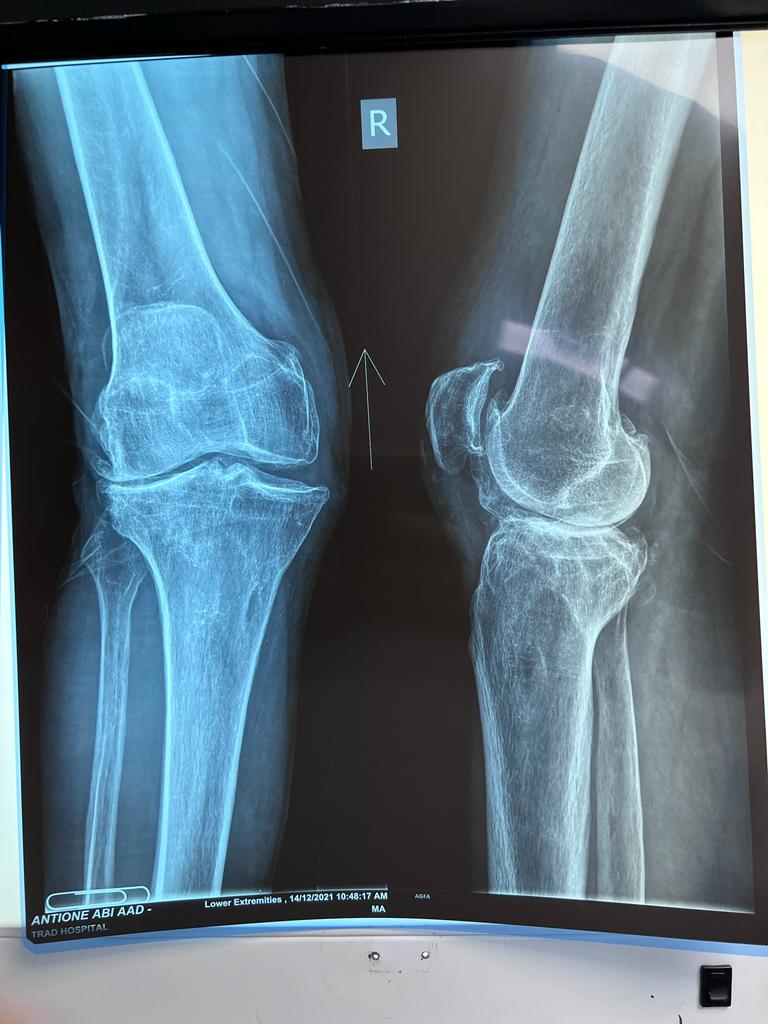

Total Knee Arthroplasty on a severe Genu Valgum

• Total Knee Arthroplasty on a severe Genu Valgum